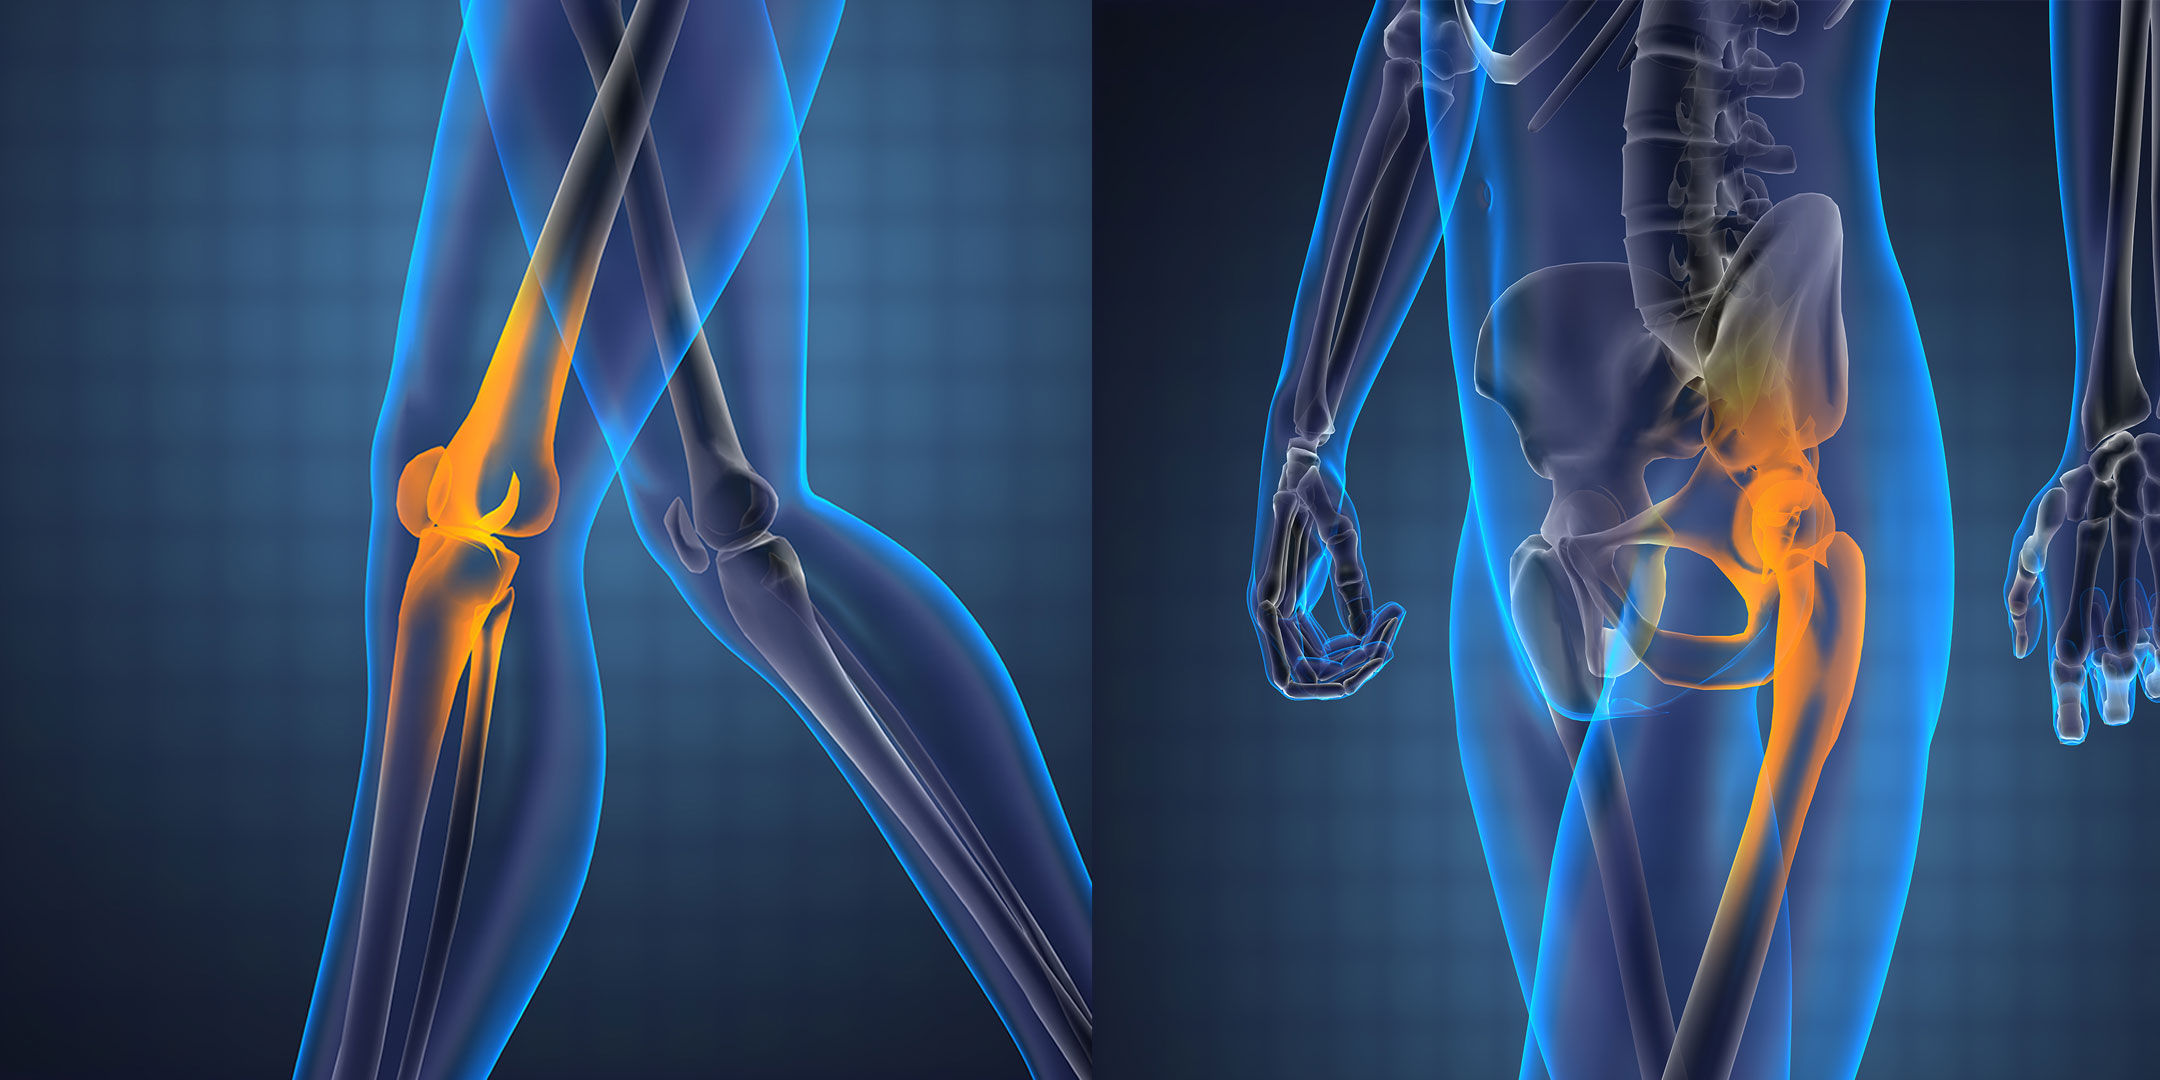

Deciding whether to undergo knee or hip replacement surgery is a significant decision that involves evaluating your pain, mobility, and overall quality of life. Both knee and hip replacements are effective treatments for joint pain and dysfunction, but the timing of the surgery is crucial for optimal outcomes. Here’s a guide to help you understand when it might be the right time for a knee or hip replacement.

Knee and hip replacement surgeries involve removing damaged parts of the joint and replacing them with artificial components. These procedures aim to alleviate pain, restore function, and improve the quality of life for individuals suffering from severe joint issues.